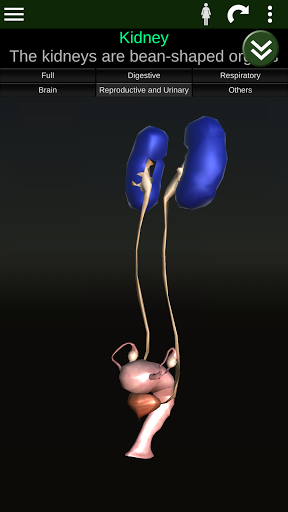

Internal Organs in 3D Anatomy لـ Vodafone Smart N9 Lite

(الأجهزة الداخلية في)

Internal Organs 3D Anatomy 3.4